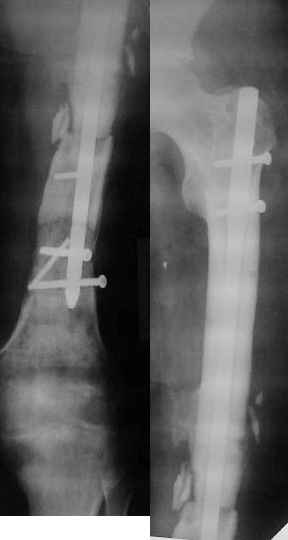

Более года назад пациент был оперирован в одном из НИИТО. При контрольном осмотре через год: болевой синдром, контрактура в локтевом суставе, патолгическая подвижность нижней трети плеча

Неудачный остеосинтез пластиной: поломка винтов, миграция фиксатора. После удаления пластины сформировался гипопластический ложный сустав нижней трети бедренной кости, укорочение н/к 5 см. Выполнялся дистакционный остеосинтез аппратом Илизарова на штифте. Зона ложного сустава "не открывалась". Через 10 месяцев, когда даже регенерат полностью перестроился, консолидации в зоне ложного сустава не наступило, несмотря на стабильную фиксацию и постоянную компрессию(штифт+аппрата на 4 кольцах).

Неудачный остеосинтез пластиной: поломка винтов. После удаления сформирался гиполастический ложный сустав. Остеосинтез АВФ, циклическая компрессия-дистракция в области ложного сустава привела к формированию хорошей рентгенологической костной мозоли. Через 1,5 месяца ходил в аппарате без дополнительных средств опоры. Через 6 месяцев после клинической пробы - демотаж. Через 4 месяца после демонтажа - лизис костной мозоли, рецидив деформации.